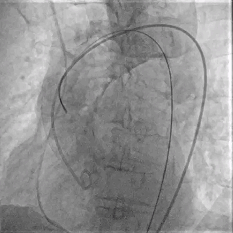

Step 5.瓣膜定位与释放:高起始位逐渐向下推送保持良好同轴性,无位移

Step 6.工作位观察:真实瓣环下方2mm,位置合适,决定释放,一次完成

Step 7.瓣膜脱钩:脱钩稳定无位移

Step 8.最终造影:真实瓣环下方3mm标准位,完全同轴,轻微反流,猪尾撤出后反流完全消失

Step 9.CuspOverlap体位验证缘对缘对齐,挂钩位于最右方,基本避开冠脉开口

Step 10.验证器械同轴性,完全同轴